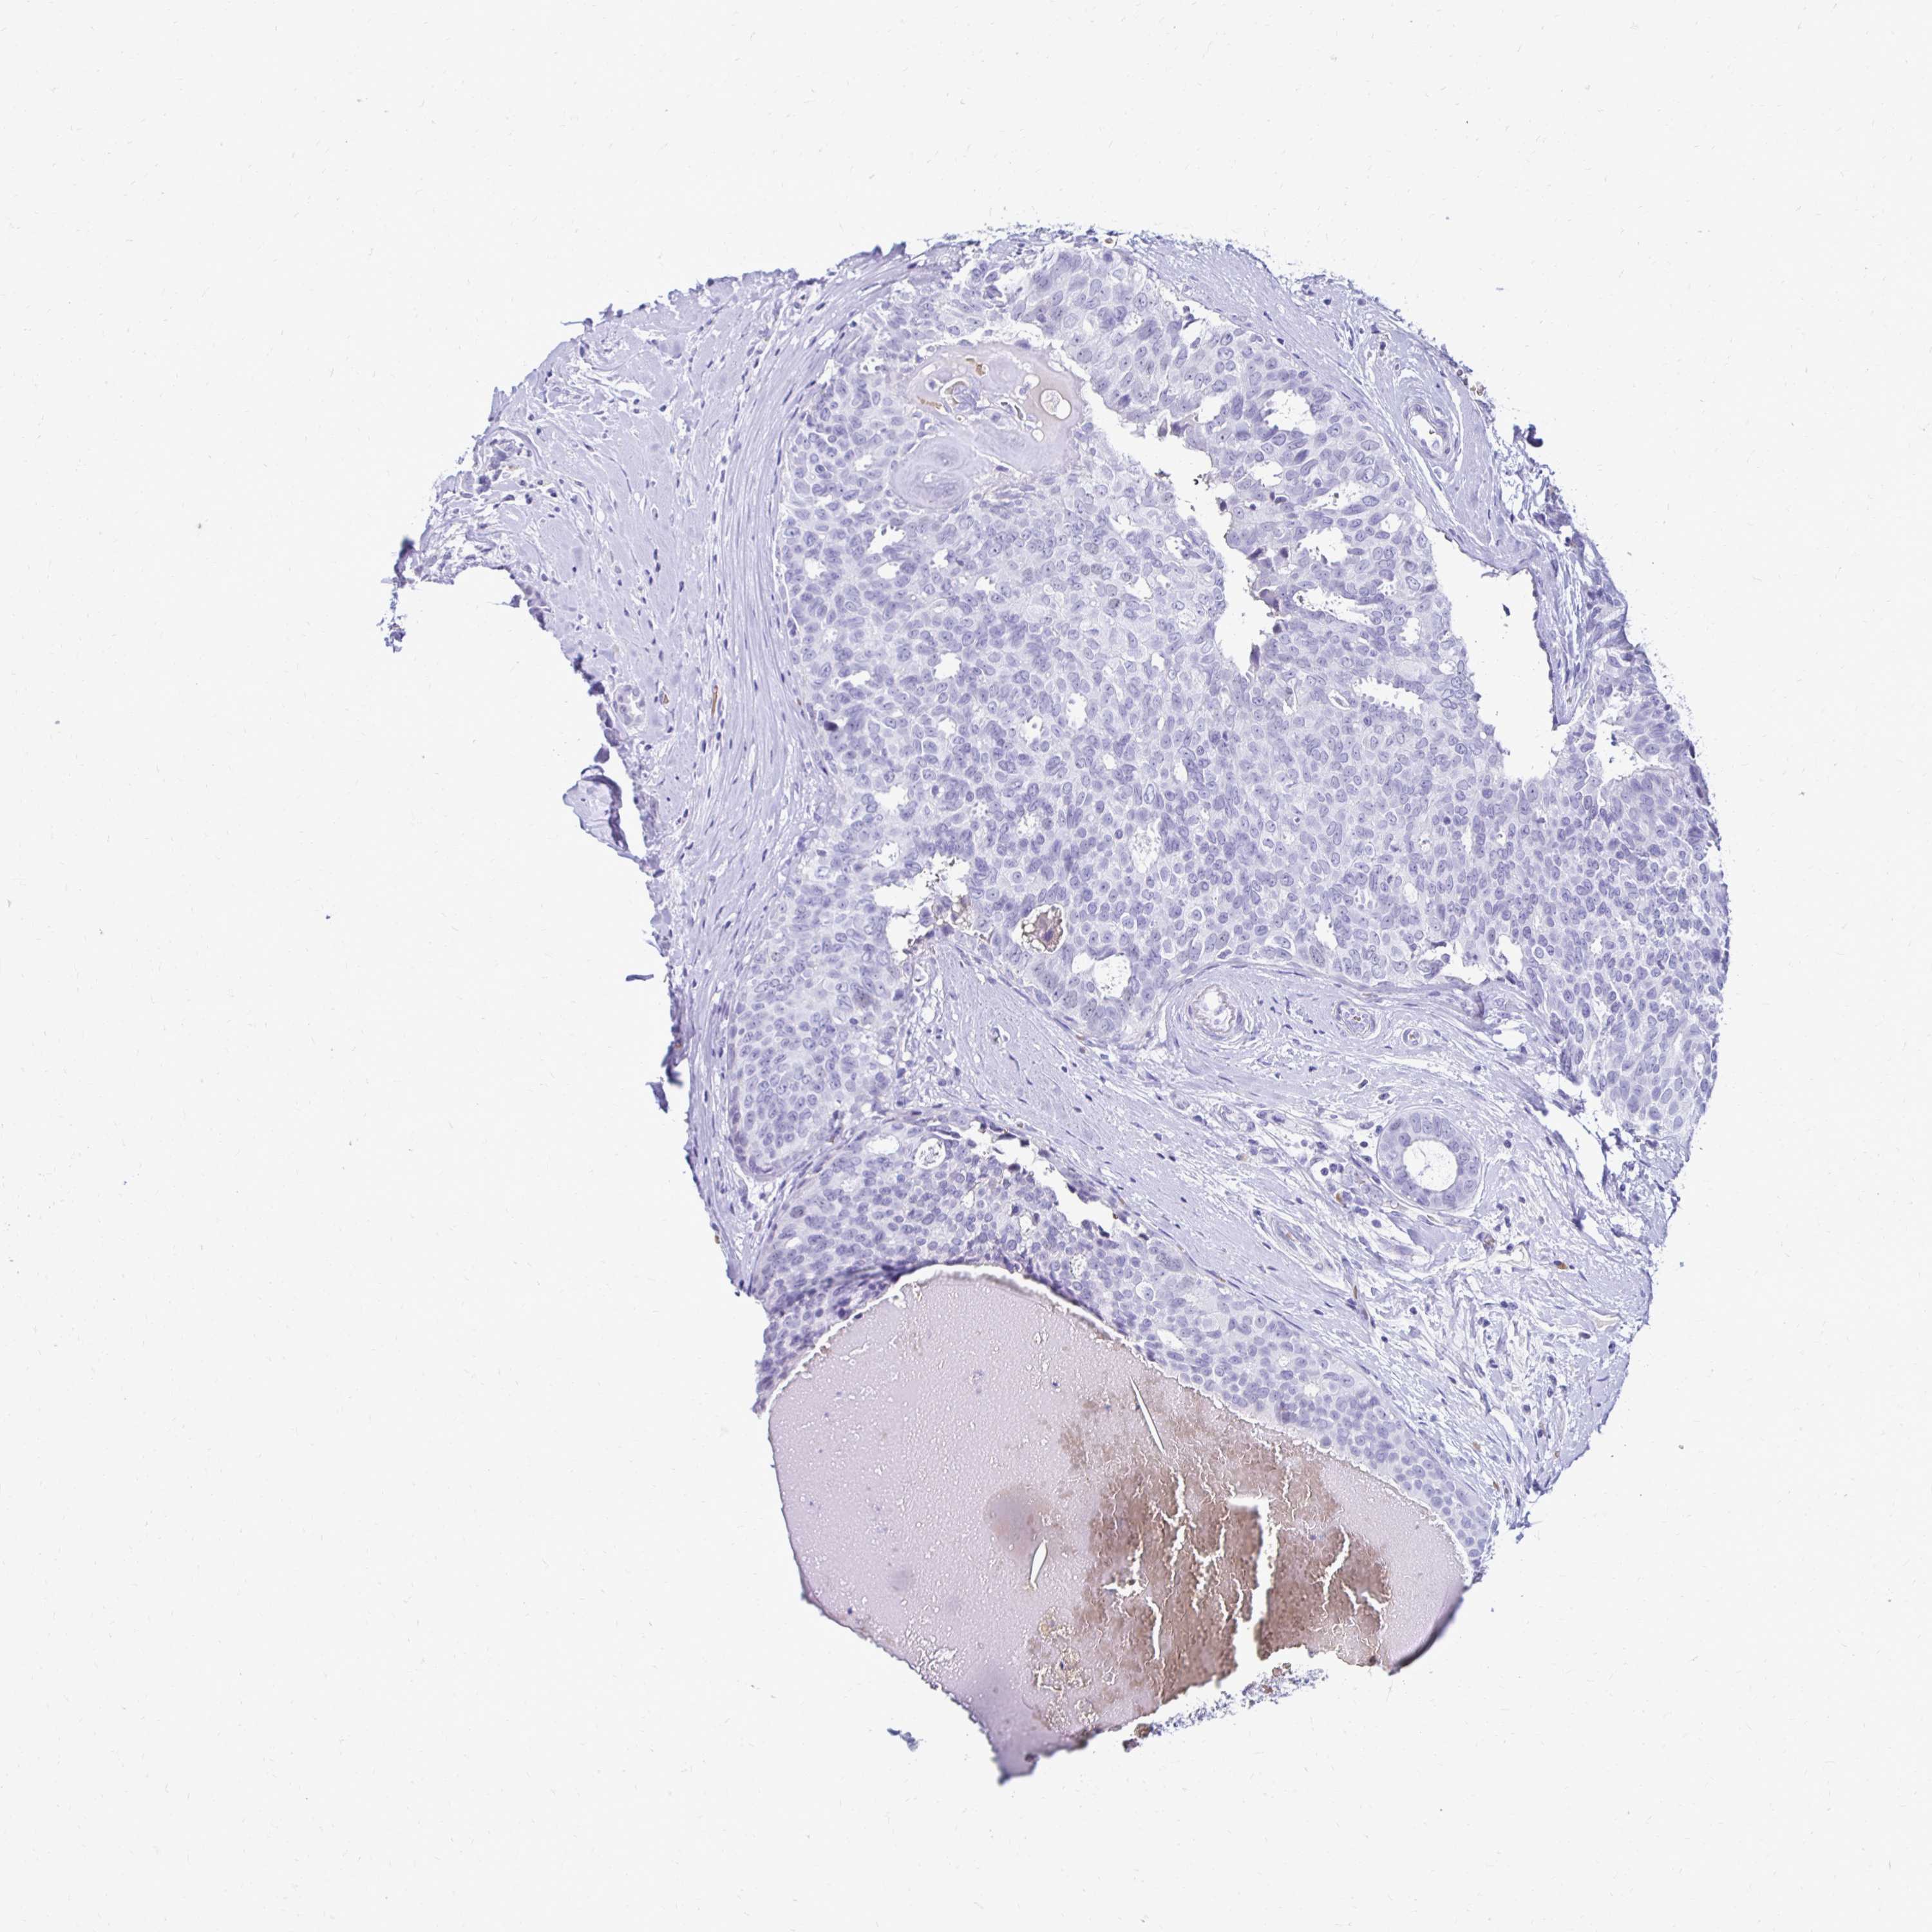

CANCER BREAST CANCER Show tissue menu

BRCA TCGA BRCA VALIDATION PROTEIN EXPRESSION

Breast cancer

Human cancer

RHBDL3 is not prognostic in Breast Invasive Carcinoma (TCGA)

Average pTPM 1.1

Number of samples 1022